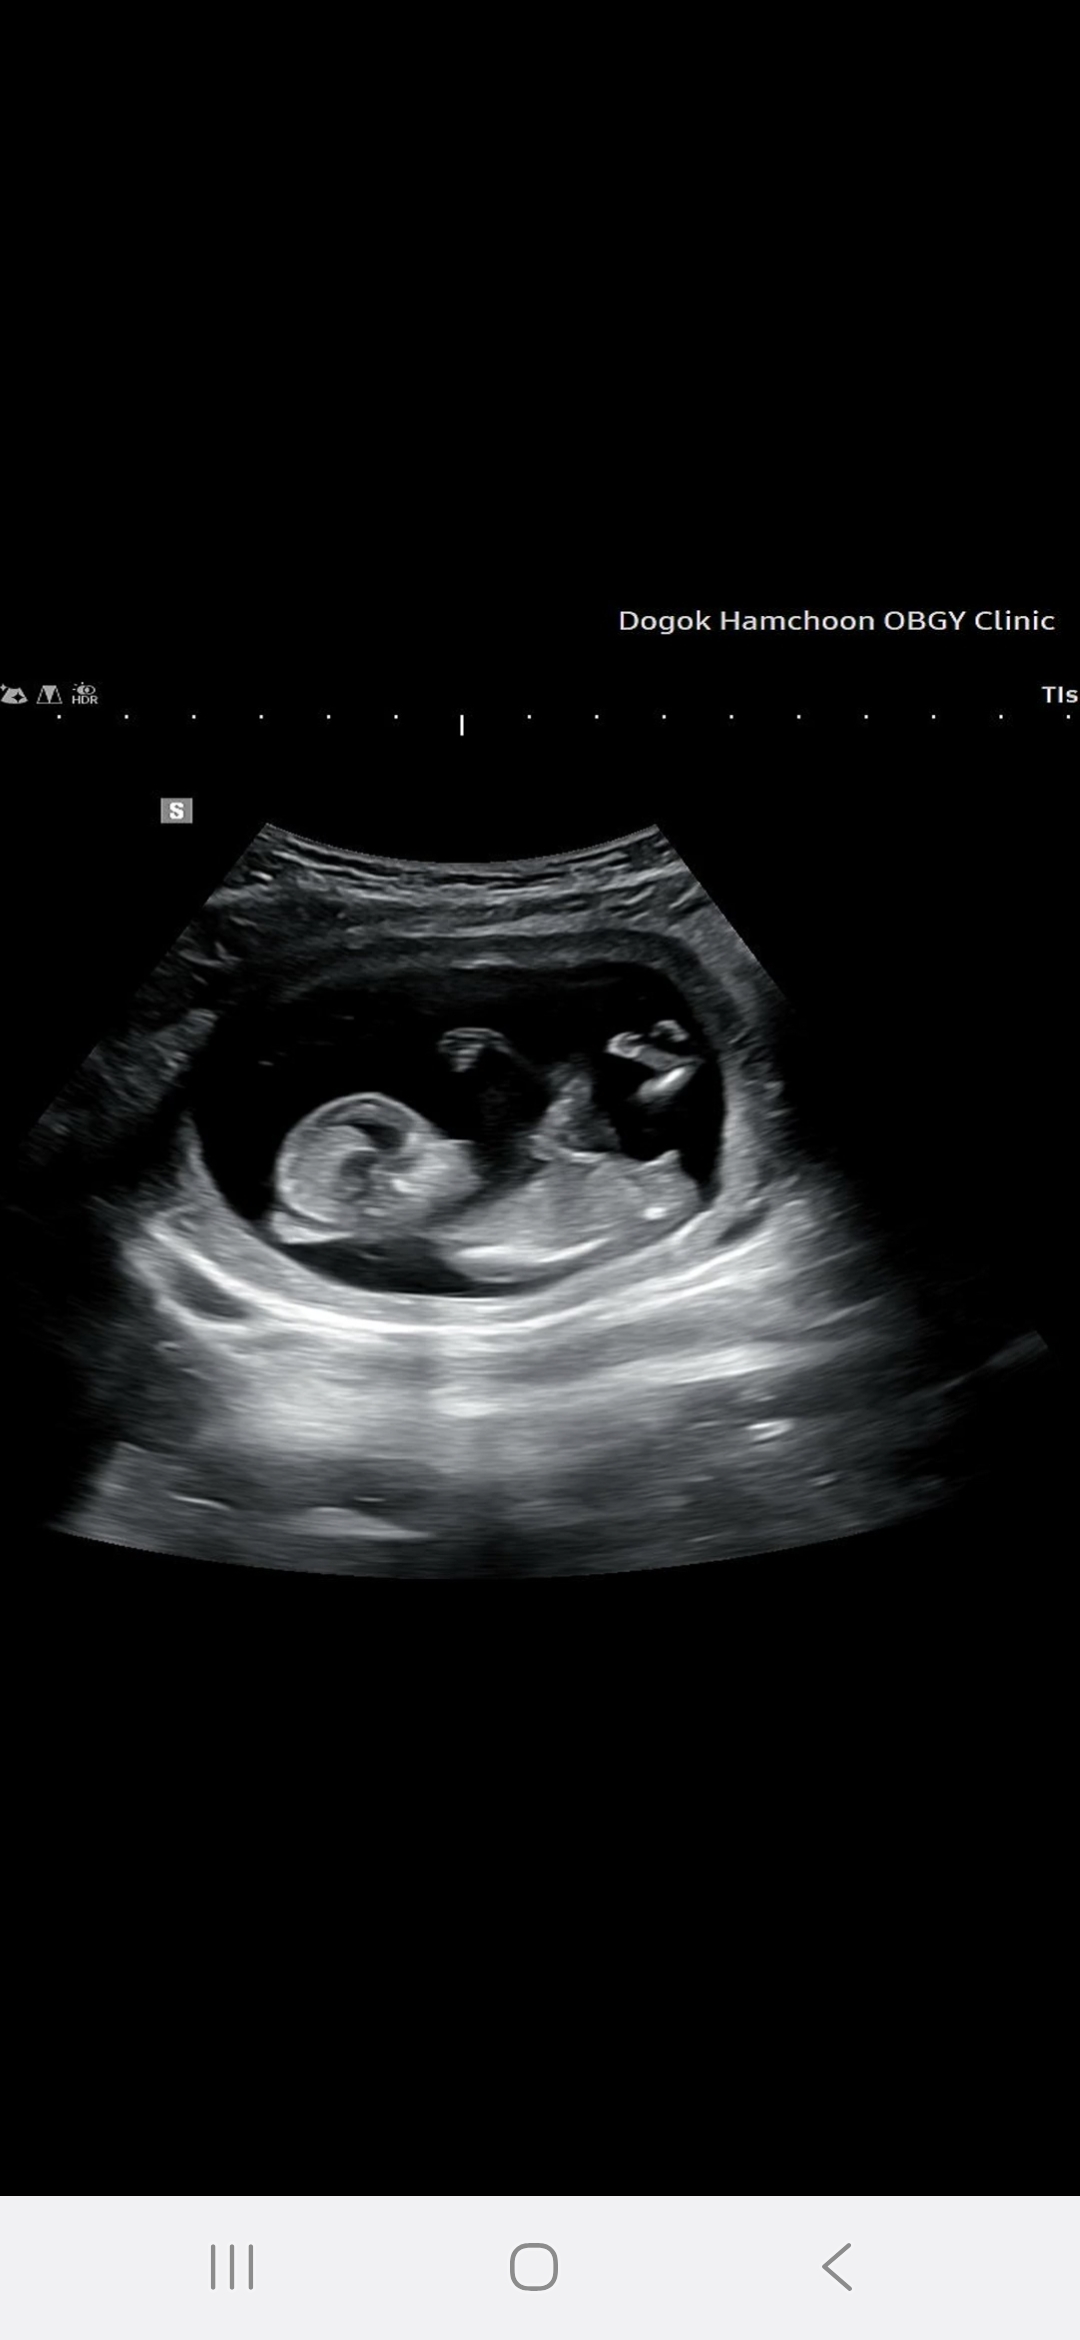

정답공개) 각도법 고수님들 고견 부탁드립니다!! 12주 4일차입니다

각도법 고수님들 고견 부탁드립니다 12주 4일차입니다. => 지금 18주 접어듭니다 ㅎㅎ 아들이라구 하시네용!!!!